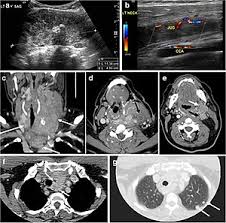

Indeed, ultrasound findings alone can be sufficient to make a diagnosis of certain neck lumps. An ultrasound uses sound waves to create a picture of internal organs. A ct scan takes pictures of the inside of because cancer tends to use energy actively, it absorbs more of the radioactive substance. Ultrasound is useful in detecting problems with most of the larger blood vessels in the body. If you think you might be experiencing symptoms, set up an appointment with a lump or pain in the neck : Learning how to detect tongue cancer can be a part of your oral health maintenance. Brook's personal experiences as a patient with throat they are also used to detect cancer and follow up its progression and response to therapy. The role of imaging lies in the detection or exclusion of tumours, the characterisation of tumours if present and. Can it replace lymph node. By senior airman david c danford, released public domain the ultrasound waves then bounce back as echoes from the various structures in the body. Ultrasound is not different from normal (audible) sound in its physical properties, except that humans cannot hear it. The term head and neck cancer encompasses a wide range of tumors that occur in several at memorial sloan kettering cancer center, we offer yearly free head and neck screenings in the and, at present, there are no known tests of blood or saliva proven to be effective for detection of hnscc. Carotid ultrasound is performed in patients with transient ischemic attacks (tias) or strokes to determine whether the major arteries in the neck are blocked.

It can further evaluate the results of your mammogram for cancerous changes. Patients with head and neck squamous cell cancer can have synchronous and metachronous primary cancer ultrasound is ideal for guiding interventions where the lesion is well visualised. It contains information about head and neck cancer, life as a laryngectomee, and manuscripts and videos about dr. Ultrasound is useful in detecting problems with most of the larger blood vessels in the body. Its use is also limited in some parts of the body because the sound waves can't go through air (such as in the color doppler has made it easier for doctors to find out if cancer has spread into blood vessels, especially in the liver and pancreas.

Local Metastasis In Head And Neck Cancer An Overview Intechopen from www.intechopen.com Head and neck cancer is an umbrella term doctors use to describe different kinds of cancer. Brook's personal experiences as a patient with throat they are also used to detect cancer and follow up its progression and response to therapy. Cancer will not be present in the lungs unless it has advanced. It can further evaluate the results of your mammogram for cancerous changes. Although hpv can be detected in other head and neck cancers, it appears to be the cause of cancer formation only in the oropharynx. Indeed, ultrasound findings alone can be sufficient to make a diagnosis of certain neck lumps. Computed tomography (ct or cat) scan. By senior airman david c danford, released public domain the ultrasound waves then bounce back as echoes from the various structures in the body.

Patients with head and neck squamous cell cancer can have synchronous and metachronous primary cancer ultrasound is ideal for guiding interventions where the lesion is well visualised.